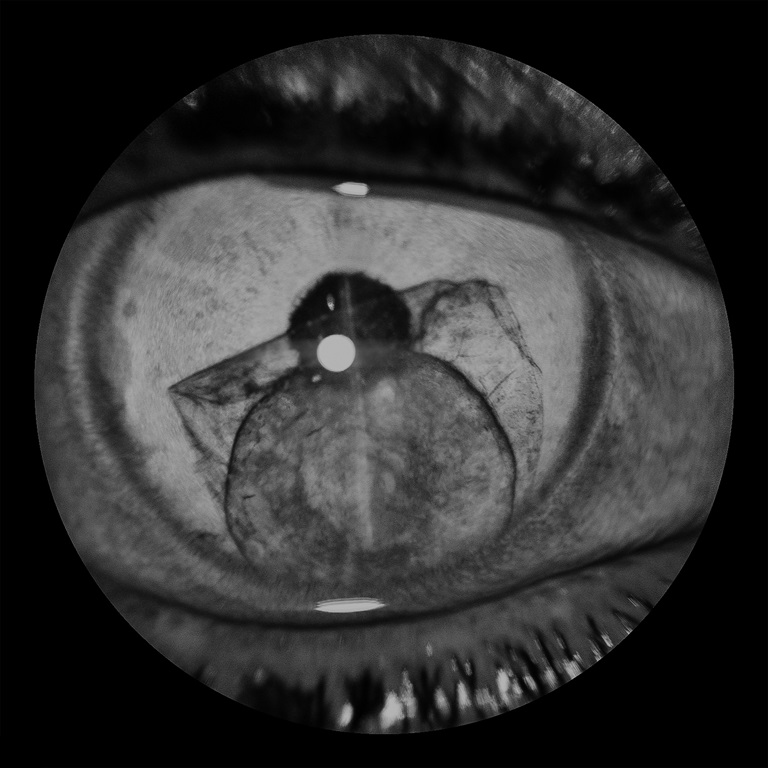

Crystal Clear Crystalline Lens in the Anterior Chamber

Presented by Shruthy Ramesh, FRCOphth, MS, DNBThis photograph received 3rd Place in the category "Monochromatic Photography" and was displayed at the 2024 ASCRS/OPS Society Exhibit.